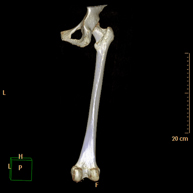

- Hip CT

Radiological examination based on an X-ray system and detectors that rotate around the patient, reconstructing the images by computer (multidetector computed tomography - MDCT) to study the bones, muscles and joints of the hips.